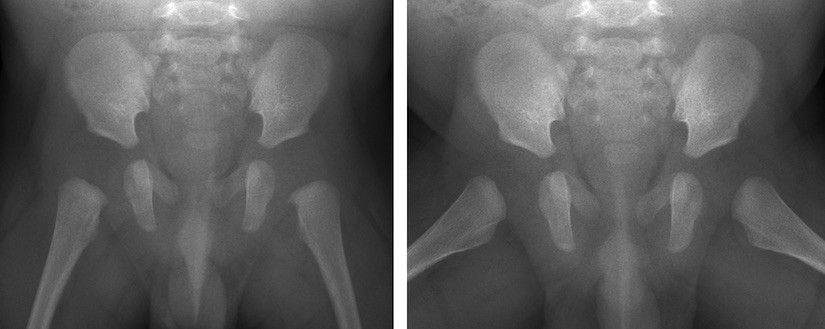

Links: voorachterwaartse röntgenfoto (AP-opname) met de benen gestrekt van het bekken van een baby van 3 maanden.

Rechts: voorachterwaartse röntgenfoto in kikkerhouding (Lauensteinopname) van het bekken van een baby van 3 maanden.

Links: voorachterwaartse röntgenfoto (AP-opname) met gestrekte benen van het bekken van een kind van 12 maanden.

Rechts: voorachterwaartse röntgenfoto in kikkerhouding (Lauensteinopname) van het bekken van een kind van 12 maanden.

Bij kinderen wordt meestal een bekkenfoto van voor naar achter gemaakt (AP-opname: anterior posterior) met de benen gestrekt. De tweede foto wordt dan gemaakt met de benen in de zogenaamde kikkerpositie. Dit heet een Lauensteinopname. Hiermee kan onder andere worden gekeken of de heupkop goed in de kom staat en kan de vorm van de heupkop in twee richtingen worden gecontroleerd.